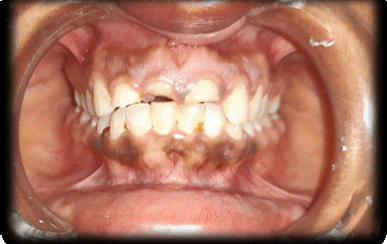

Dr. Ananya graduated from the prestigious Manipal College of Dental Sciences, Manipal with a BDS degree and completed her postgraduation (MDS) in Conservative Dentistry and Endodontics from IDS, Bareilly. She has been passionately practicing dentistry since then. With the desire to pursue both academics and also run a clinical practice she continues to serve as a teaching faculty at a dental college in Lucknow and manages her clinic in the evening. Her meticulous approach, experience and desire to provide the best treatment has always enabled her to save teeth in a relatively painless manner. She is also a member of